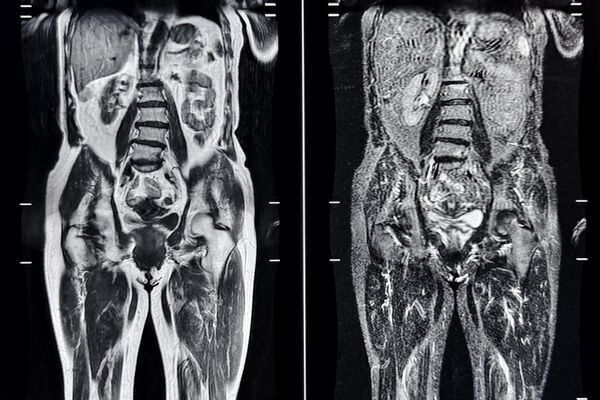

Von Kopf bis Fuß durchschaut.

Dank des enormen technischen Fortschritts der MRT-Forschung, insbesondere der MR-Gradiententechnik und der Herstellung von organspezifischem Kontrastmittel, ist es uns heute möglich, den gesamten menschlichen Körper darzustellen – und dies nicht-invasiv, also ohne Eindringen in den Körper.